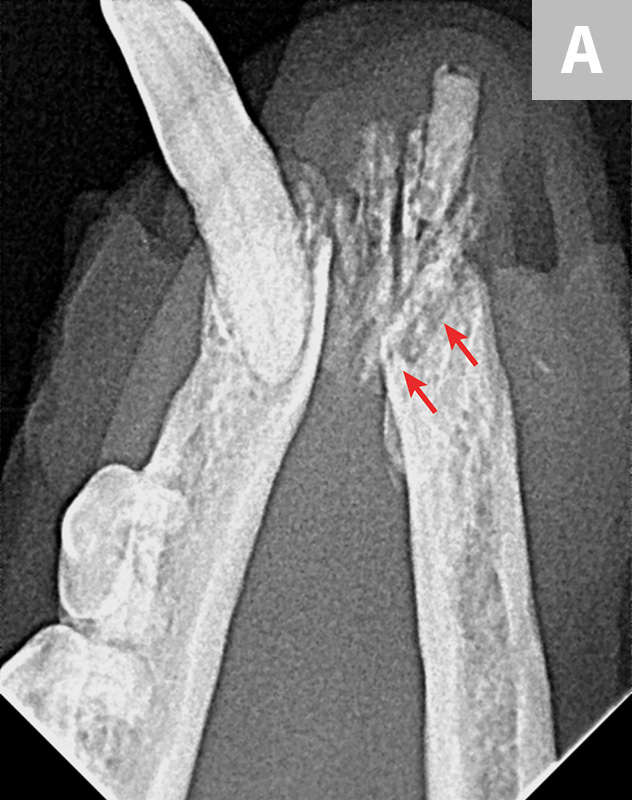

Most Common Complication Of Tooth Extraction . It has been reported that the surgical extraction of a tooth is the most common surgical procedure in the united states. Several factors may necessitate tooth extraction, including: Most frequent complications of tooth extraction include dry socket (4.6%) [7, 8]. Dry socket, bleeding and root fracture). Dry socket was the most predominant complication. Severe tooth decay renders the tooth unrestorable. Nerve injuries were the most common (7.2%). Exodontia is removal of the tooth from its alveolar socket and supportive. An overview of common complications of dental extractions and their management (e.g. 1 a 2015 study by gilbert et al 2 found that 64% of general dentists routinely remove teeth. A common occurrence during tooth removal is a fractured and retained root (figure 1). The complication rate was 8.4% for the 1,199 wisdom teeth extracted.

The complication rate was 8.4% for the 1,199 wisdom teeth extracted. A common occurrence during tooth removal is a fractured and retained root (figure 1). An overview of common complications of dental extractions and their management (e.g. Dry socket was the most predominant complication. It has been reported that the surgical extraction of a tooth is the most common surgical procedure in the united states. Nerve injuries were the most common (7.2%). Severe tooth decay renders the tooth unrestorable. Several factors may necessitate tooth extraction, including: 1 a 2015 study by gilbert et al 2 found that 64% of general dentists routinely remove teeth. Most frequent complications of tooth extraction include dry socket (4.6%) [7, 8].

Most Common Complication Of Tooth Extraction Nerve injuries were the most common (7.2%). A common occurrence during tooth removal is a fractured and retained root (figure 1). It has been reported that the surgical extraction of a tooth is the most common surgical procedure in the united states. Nerve injuries were the most common (7.2%). Dry socket, bleeding and root fracture). An overview of common complications of dental extractions and their management (e.g. Exodontia is removal of the tooth from its alveolar socket and supportive. Severe tooth decay renders the tooth unrestorable. Most frequent complications of tooth extraction include dry socket (4.6%) [7, 8]. The complication rate was 8.4% for the 1,199 wisdom teeth extracted. 1 a 2015 study by gilbert et al 2 found that 64% of general dentists routinely remove teeth. Dry socket was the most predominant complication. Several factors may necessitate tooth extraction, including:

Complications occur During Dental Extraction and their Management Most Common Complication Of Tooth Extraction Nerve injuries were the most common (7.2%). A common occurrence during tooth removal is a fractured and retained root (figure 1). It has been reported that the surgical extraction of a tooth is the most common surgical procedure in the united states. Dry socket, bleeding and root fracture). Several factors may necessitate tooth extraction, including: The complication rate was 8.4%. Most Common Complication Of Tooth Extraction.

(A) Tooth 13 had to be extracted due to an endodontic complication and Most Common Complication Of Tooth Extraction Severe tooth decay renders the tooth unrestorable. Dry socket was the most predominant complication. 1 a 2015 study by gilbert et al 2 found that 64% of general dentists routinely remove teeth. A common occurrence during tooth removal is a fractured and retained root (figure 1). It has been reported that the surgical extraction of a tooth is the most. Most Common Complication Of Tooth Extraction.